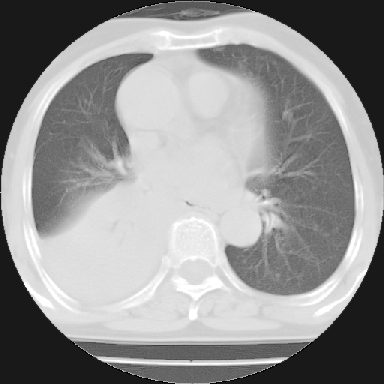

以下是引用苯小孩在2007-4-13 16:20:00的发言:[br]1、右下肺中央型肺癌并阻塞性肺不张、肺内转移、胸椎右侧附件亦有转移<横断层面第8层>.[br]2、右侧胸腔积液.

以下是引用swyyy2007在2007-4-13 15:31:00的发言:[br]右肺门下区肿块,右肺下叶支气管阻塞,右肺下叶不张,右侧大量胸腔积液,右肺中叶见结节状高密度影,边缘清,纵隔内见肿大淋巴结。首先考虑右下肺中心型肺癌伴右肺下叶不张、中叶、纵隔淋巴结转移。右侧胸腔积液。